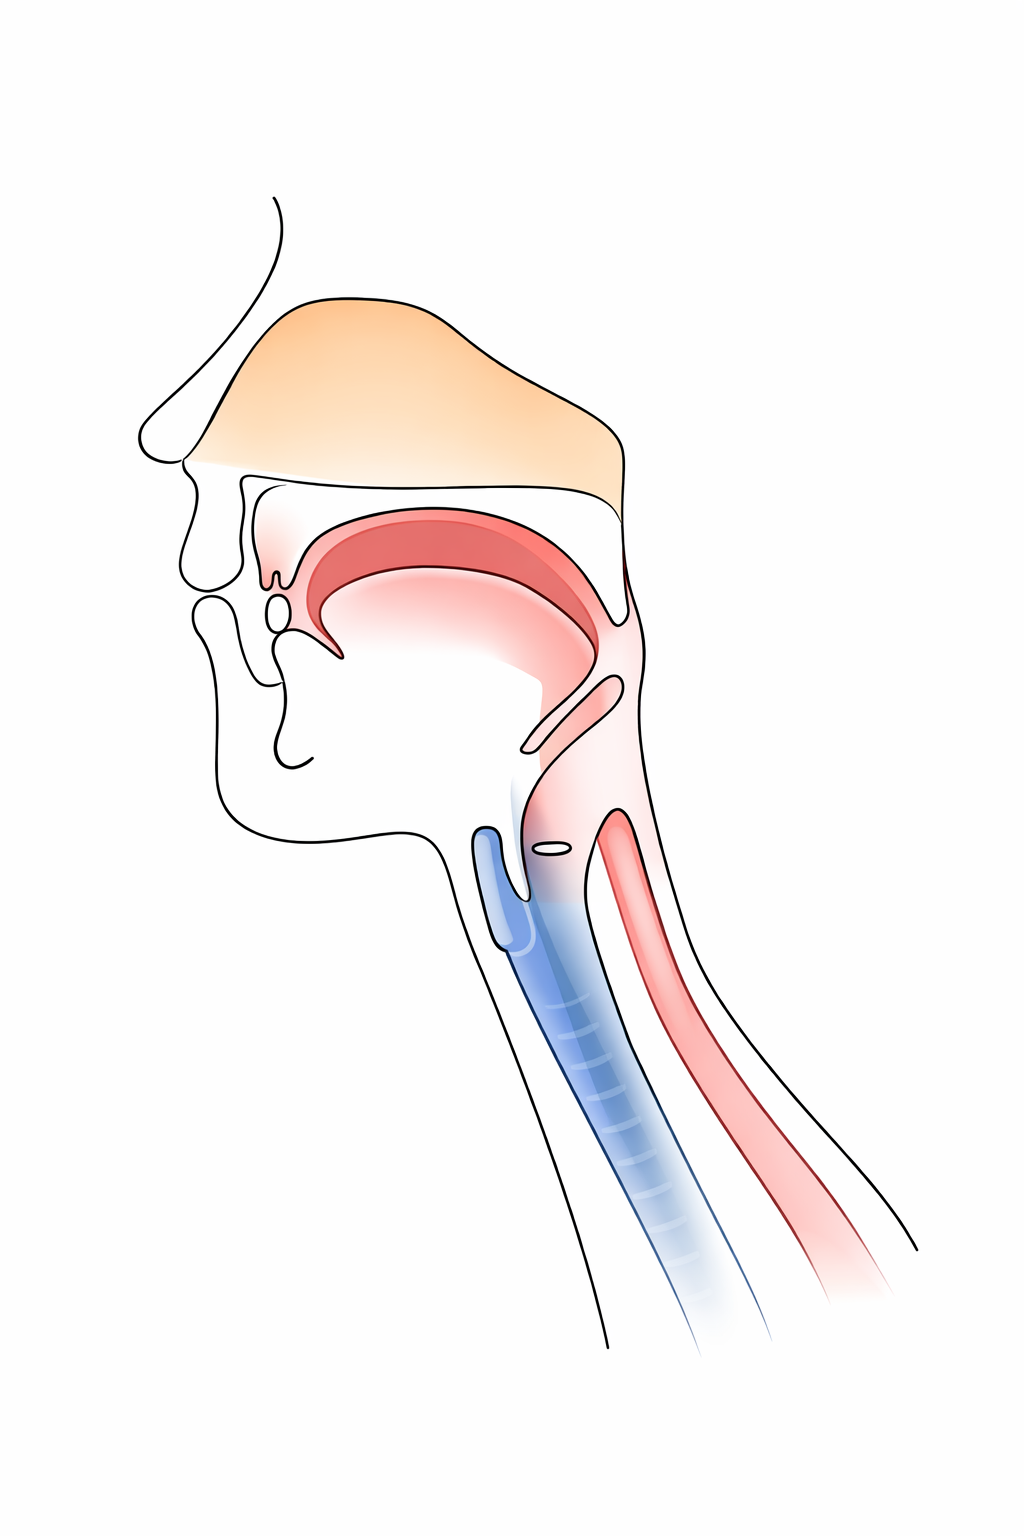

舌接触補助床とは

舌接触補助床(PAP)とは,手術やけがなどで舌(した)の一部がなくなった方や,脳梗塞などの病気で舌の動きが弱くなってご飯が食べられない方や,うまく言葉を話せない方のために作る,舌の動きを助けるための特別な入れ歯の一種です.上あごの入れ歯や装置の一部の厚みを増やすことで,舌と上あごの接触を良くし,咀嚼(そしゃく)や飲み込み,発音などのお口の機能の改善を図る装置です.

舌は,食べ物を噛んで飲み込むときや,言葉を発音するときに大切な役割を担っています.しかし,舌の一部を失ったり,動きが制限されると,

舌接触補助床は,失われた舌の高さや届く範囲を入れ歯や装置の“厚み”を増やしたり調整したりすることで,舌が上あごに接触しやすくなるようにサポートすることで,食事や会話をより自然に行えるようにします.